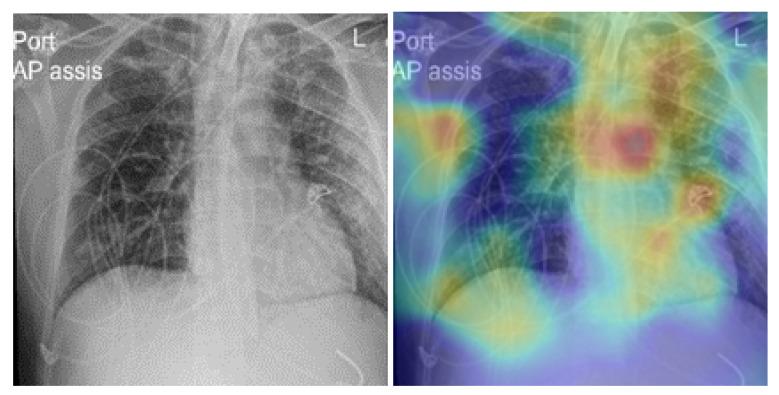

COVID-19,which is caused by the severe acute respiratory syndrome coronavirus 2 (SARS-CoV-2), is one of the worst pandemics in recent history. The identification of patients suspected to be infected with COVID-19 is becoming crucial to reduce its spread. We aimed to validate and test a deep learning model to detect COVID-19 based on chest X-rays. The recent deep convolutional neural network (CNN) RegNetX032 was adapted for detecting COVID-19 from chest X-ray (CXR) images using polymerase chain reaction (RT-PCR) as a reference. The model was customized and trained on five datasets containing more than 15,000 CXR images (including 4148COVID-19-positive cases) and then tested on 321 images (150 COVID-19-positive) from Montfort Hospital. Twenty percent of the data from the five datasets were used as validation data for hyperparameter optimization. Each CXR image was processed by the model to detect COVID-19. Multi-binary classifications were proposed, such as: COVID-19 vs. normal, COVID-19 + pneumonia vs. normal, and pneumonia vs. normal. The performance results were based on the area under the curve (AUC), sensitivity, and specificity. In addition, an explainability model was developed that demonstrated the high performance and high generalization degree of the proposed model in detecting and highlighting the signs of the disease. The fine-tuned RegNetX032 model achieved an overall accuracy score of 96.0%, with an AUC score of 99.1%. The model showed a superior sensitivity of 98.0% in detecting signs from CXR images of COVID-19 patients, and a specificity of 93.0% in detecting healthy CXR images. A second scenario compared COVID-19 + pneumonia vs. normal (healthy X-ray) patients. The model achieved an overall score of 99.1% (AUC) with a sensitivity of 96.0% and specificity of 93.0% on the Montfort dataset. For the validation set, the model achieved an average accuracy of 98.6%, an AUC score of 98.0%, a sensitivity of 98.0%, and a specificity of 96.0% for detection (COVID-19 patients vs. healthy patients). The second scenario compared COVID-19 + pneumonia vs. normal patients. The model achieved an overall score of 98.8% (AUC) with a sensitivity of 97.0% and a specificity of 96.0%. This robust deep learning model demonstrated excellent performance in detecting COVID-19 from chest X-rays. This model could be used to automate the detection of COVID-19 and improve decision making for patient triage and isolation in hospital settings. This could also be used as a complementary aid for radiologists or clinicians when differentiating to make smart decisions.

COVID-19 是由严重急性呼吸综合征冠状病毒 2(SARS-CoV-2)引起的,是最近历史上最严重的大流行之一。识别疑似感染 COVID-19 的患者对于减少其传播至关重要。我们旨在验证和测试一种基于胸部 X 光片检测 COVID-19 的深度学习模型。最近的深度卷积神经网络(CNN)RegNetX032 经过适应,可使用聚合酶链反应(RT-PCR)作为参考,从胸部 X 光(CXR)图像中检测 COVID-19。该模型在包含超过 15000 张 CXR 图像(包括 4148 例 COVID-19 阳性病例)的五个数据集上进行了定制和训练,然后在蒙福特医院的 321 张图像(150 例 COVID-19 阳性病例)上进行了测试。五个数据集的 20%的数据用于超参数优化的验证数据。模型处理每张 CXR 图像以检测 COVID-19。提出了多二进制分类,例如:COVID-19 与正常,COVID-19+肺炎与正常,肺炎与正常。性能结果基于曲线下面积(AUC)、敏感性和特异性。此外,还开发了一个可解释性模型,该模型证明了所提出的模型在检测和突出疾病迹象方面具有出色的性能和高度的泛化能力。经过微调的 RegNetX032 模型的整体准确率达到 96.0%,AUC 评分为 99.1%。该模型在检测 COVID-19 患者的 CXR 图像中的迹象方面表现出优越的敏感性,达到 98.0%,在检测健康 CXR 图像方面具有 93.0%的特异性。第二个场景比较了 COVID-19+肺炎与正常(健康 X 射线)患者。该模型在蒙福特数据集上的总体评分为 99.1%(AUC),具有 96.0%的敏感性和 93.0%的特异性。对于验证集,该模型的平均准确率为 98.6%,AUC 评分为 98.0%,敏感性为 98.0%,特异性为 96.0%用于检测(COVID-19 患者与健康患者)。第二个场景比较了 COVID-19+肺炎与正常患者。该模型的总体评分为 98.8%(AUC),敏感性为 97.0%,特异性为 96.0%。该强大的深度学习模型在从胸部 X 光片中检测 COVID-19 方面表现出出色的性能。该模型可用于自动检测 COVID-19,并提高医院环境中患者分诊和隔离的决策能力。当进行区分以做出明智决策时,它也可以作为放射科医生或临床医生的辅助工具。